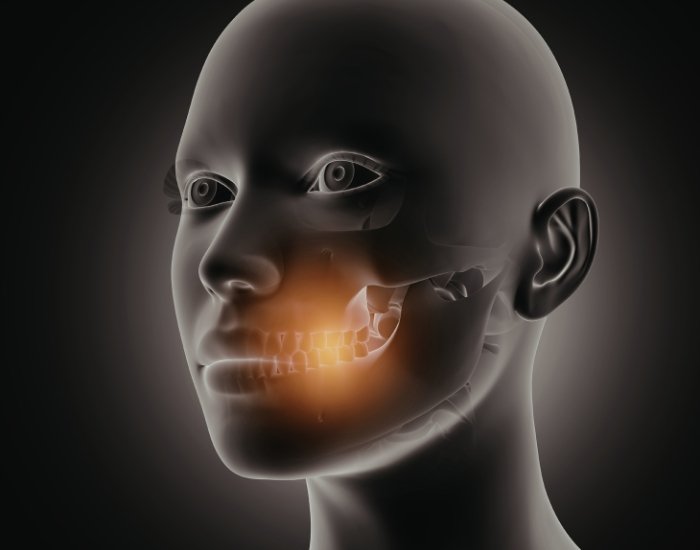

For many people with temporomandibular joint (TMJ) discomfort or dysfunction, traditional treatments like oral splints, physical therapy, or pain medications may provide only limited relief. In that context, TMJ Botox before and after results have gained attention as a treatment option aimed at reducing muscle tension, easing pain, and improving jaw mobility. But what can you realistically expect from this treatment, how does it work, and is it right for you? In this comprehensive guide, we explore everything from how Botox helps relax muscles to the typical timeline of results, potential risks, and real-world considerations so you can make informed decisions about your TMJ care.

TMJ Botox refers to injections of botulinum toxin into specific jaw muscles that are overactive or tense in individuals with TMJ disorders. The toxin temporarily blocks nerve signals that tell muscles to contract, which leads to muscle relaxation and reduced force during activities like chewing or clenching. The treatment is not FDA-approved specifically for TMJ disorders, meaning it’s often used “off-label” after more conservative therapies have been tried first.

Unlike cosmetic Botox, which is aimed at reducing wrinkles, TMJ Botox targets the masseter, temporalis, and other jaw-related muscles to reduce hyperactivity that can contribute to pain and dysfunction.

When injected into jaw muscles, botulinum toxin interrupts communication between nerves and muscles. This causes the muscle fibers to relax and contract less forcefully. With reduced contraction, muscle tension decreases, which can ease pain, prevent grinding, and help break the cycle of dysfunction that commonly contributes to TMJ pain and tightness.